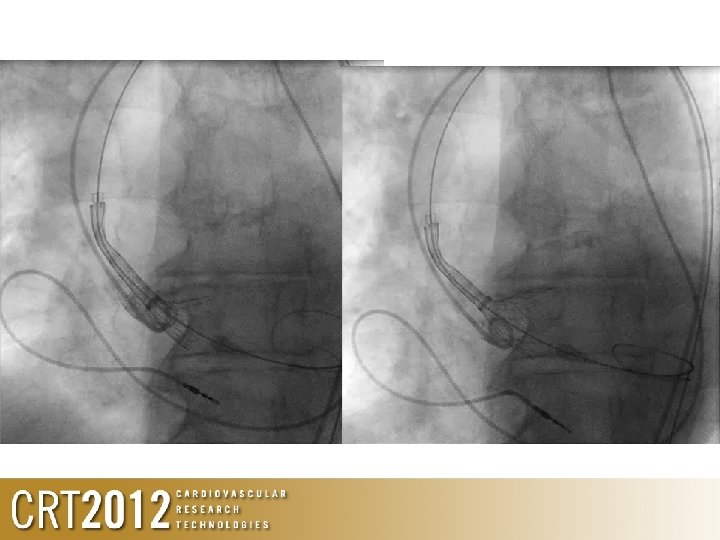

Positioning of stiff wire • After crossing AV, exchange to pigtail, ensure pigtail is free • Advance stiff wire with pigtail

Positioning of valve

What about Edwards valve? 2 D • • ‘Rules’ Usually aim for 50: 50 If LV severely hypertrophied, go more ventricular If LV dilated/impaired and STJ small, go more aortic Ensure adequate pacing, with significant drop in cardiac output during valve deployment